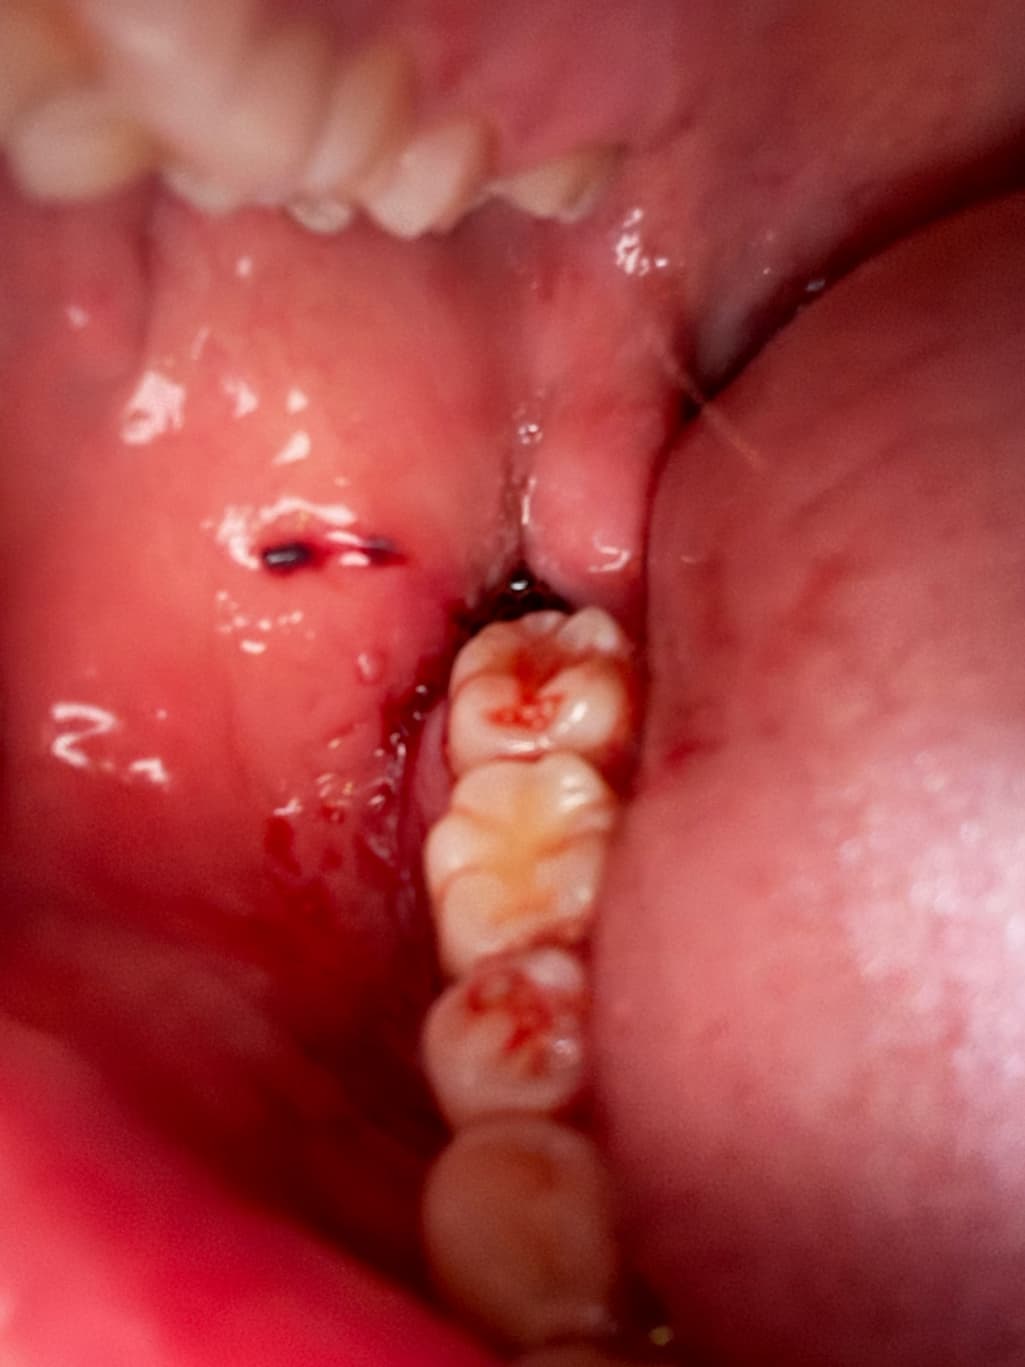

사랑니발치하고 현재 출혈이 멈춘 상태인가요?

오후2시쯤 뽑고 거즈물고 병원가서 5시쯤 거즈새로갈고 꾹물다가 오후8시쯤 땠어요.

침이 많이나와서 자주삼키는데 피는 고일정도로는 흐르진않는거같고 발치한부분잇몸으로 조금 흘러멈춘정도로 나온거같아요. 지혈된건가요???

사랑니발치하고 현재 출혈이 멈춘 상태인가요? -> 네 출혈이 심하지 않아보입니다 너무 걱정마세요

사진으로 봤을 경우에는 아직 출혈이 되고 있는 것으로 보입니다. 사랑니를 발치한 부위가 자극되지 않도록 하시고 거즈를 더 물고 있는 것이 좋을 것으로 생각됩니다

지혈은, 된 것이 맞으며 어느정도. 피가 새어나오는 것은 며칠 정도는 더 지속될 것 입니다.